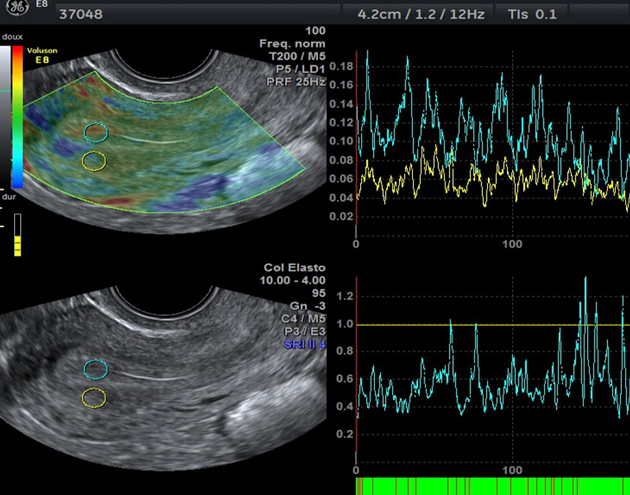

Contractilité utérine et élastographie, facteurs pronostiques en insémination intra-utérine

Dr Laura Alter

CHL Poissy/St-Germain-en-Laye - Poissy

La fréquence et l'intensité des contractions utérines au moment de l'insémination intra-utérine ont un impact sur les taux de grossesses. En dehors de la grossesse, l'utérus se contracte de manière cyclique. En cycle spontané, les contractions utérines sont fréquentes en période ovulatoire et rares pendant la fenêtre implantatoire. En Fécondation In Vitro...